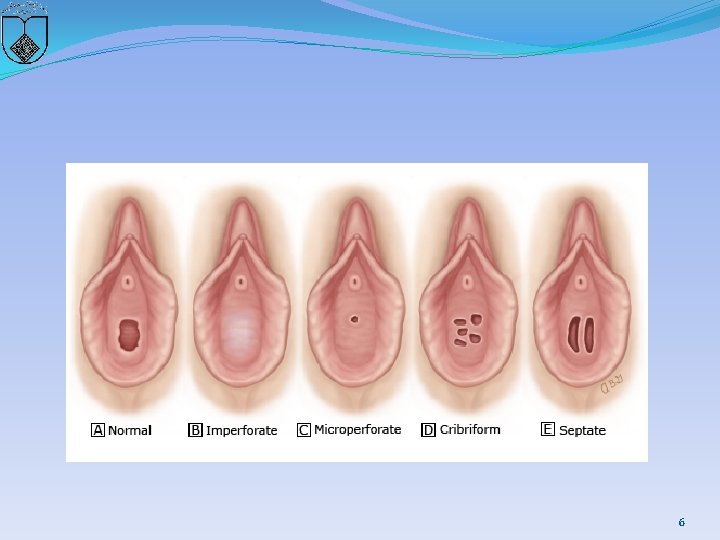

�Hymen � The vaginal lumen is separated from the urogenital sinus by the hymenal membrane. � The hymen usually ruptures before birth due to degeneration of the central epithelial cells. �However, a thin fold of mucous membrane persists around the vaginal introitus. �The hymenal membrane consists of fibrous connective tissue attached to the vaginal wall. �Hymenal anomalies are derived from incomplete degeneration of the central portion of the hymen. � These anatomic variants include imperforate, microperforate, septate, and cribriform hymens 5

6